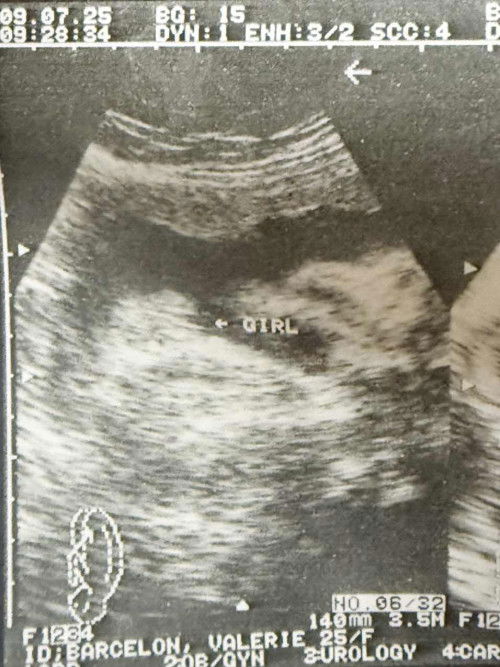

Pano ba makita at malaman if girl talaga yan? Kahit girl na talaga nakalagay jan? šŸ˜… ano ba basehan mga miii?? #AskingAsA2ndtimemom ##askmommies #Sharingdong_Bund #sharing

if its a girl, burger-like image. with 3 lines. if its a boy, turtle-like image.

Burger like image na po ba yan? Huhu. Pasensiya na, hindi kasi ako marunong tumingin tapos may mga what ifs pa ko 😩